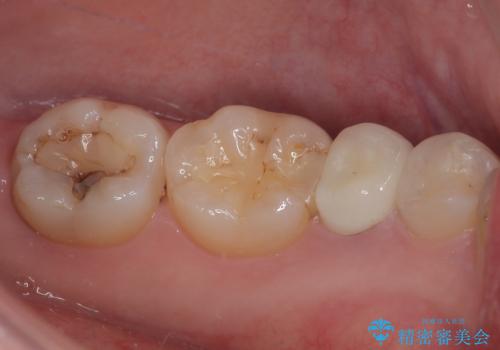

適合の良い被せものが入り、審美面も気に入っていただけました。被せものが割れていたという経緯もあったため少しだけ被せものの厚みを多めに確保してあります。

当院で矯正治療も行っているため、今後もリテーナーを使ってもらいながら経過を観察していきます。